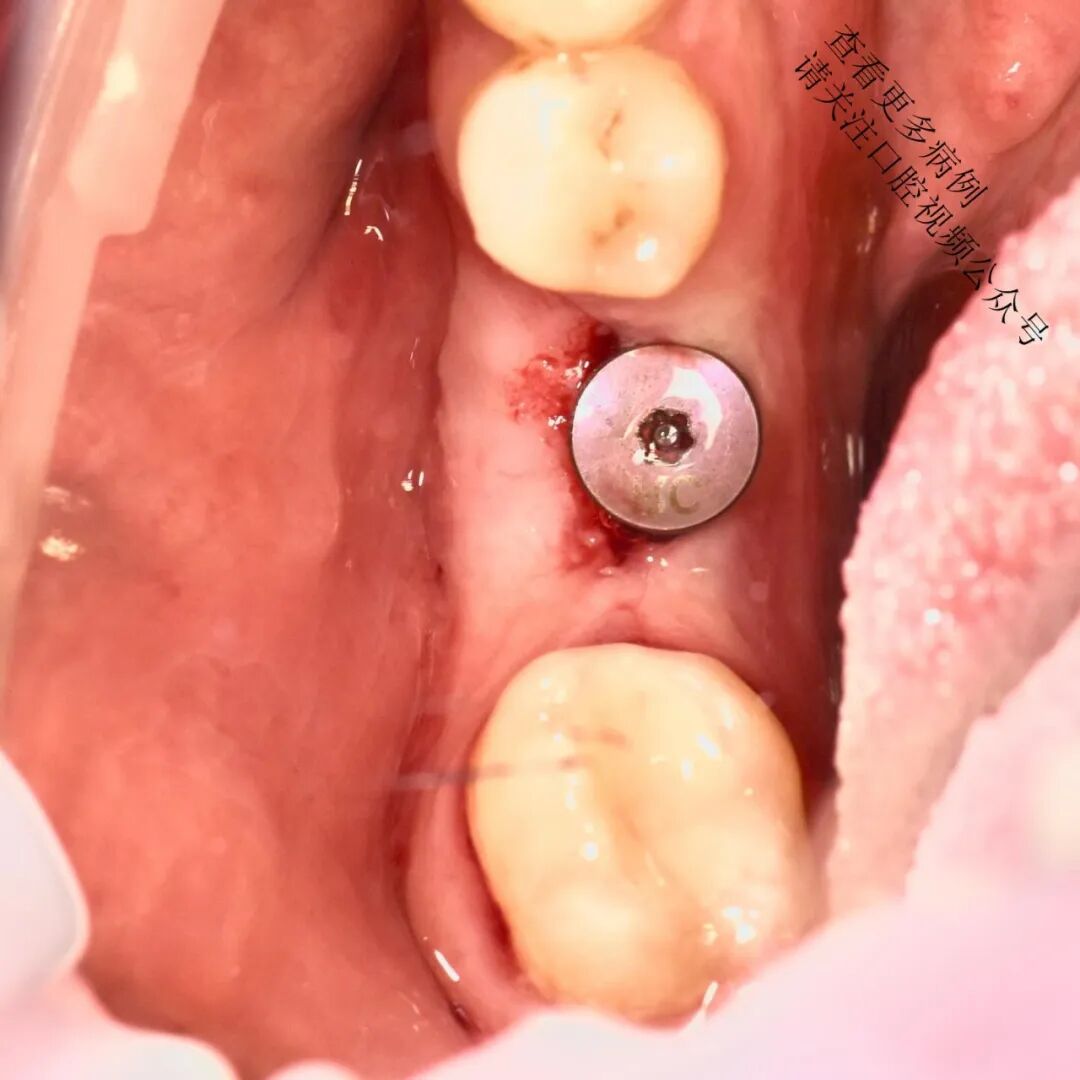

使用不可吸收缝线(如Prolene 6/0)将移植片紧密固定于骨膜上

术后4个月复查

临床意义: 此类手术常用于改善种植体周围软组织质量,增强角化龈宽度与厚度,从而提升长期美学和功能稳定性。